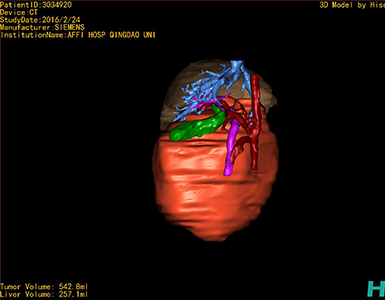

将0.625mm双源薄层CT资料的静脉期和动脉期Dicom格式文件导入海信CAS系统。

通过调节窗宽窗位调整CT序号,对肿瘤,肝实质,胆囊,下腔静脉,肿瘤,肝动脉、门静脉及肝静脉等进行三维重建;系统自动计算肿瘤体积和肝脏体积。

模拟手术操作,自动计算切除肿瘤体积。肝脏体积为257.1ml,肿瘤体积为542.8ml,肿瘤体积为肝脏体积的2.11倍,通过比对6-9月正常肝脏体积为257.75±51.05 ml,通过术前模拟手术,精准判断切除后剩余肝脏体积能耐受,避免肝衰竭发生。

术前三维重建:重建图片